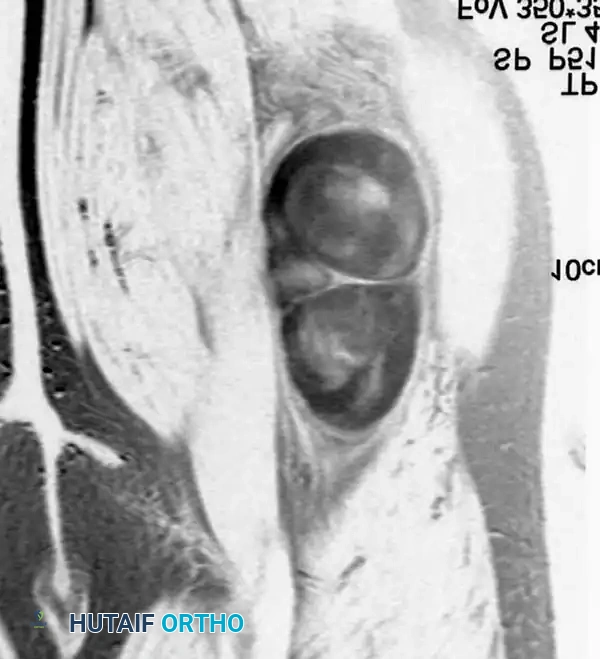

BENIGN TUMORS AND TUMOR-LIKE LESIONS Surgical Diagram

MRI demonstrating a fusiform mass along the peroneal nerve. The contrast-enhanced, fat-suppressed axial image shows peripheral enhancement with central low signal, classic for a schwannoma.